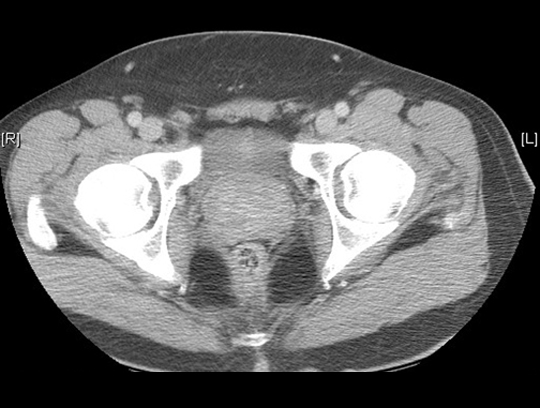

Identify the rectum and prostate in this CT. Click the image for labeling.